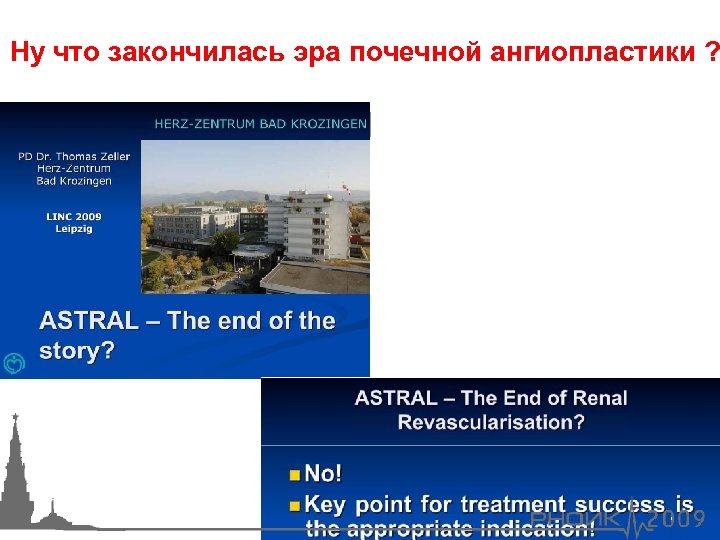

Ну что закончилась эра почечной ангиопластики ?

Ну что закончилась эра почечной ангиопластики ?